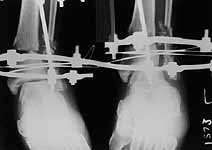

Middle aged adult was injured while travelling in a train(accidentally put his leg out). Presented with injury to left lower leg. Lacerated wound over the fibular fracture. Also another wound over the foot anterolaterally. No deficits.

On day one wound debridement followed by calcaneal traction done. Needs further stabilisation and a small split graft laterally. At present the fragments are putting pressure on the anterior skin. Will be happy to get your opinion on possible methods of stabilisation.

Day 1

Traction